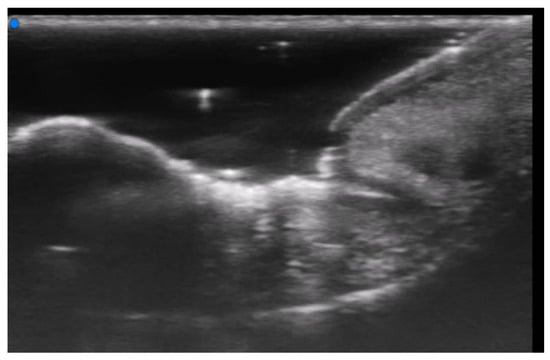

- Wortsman, X.; Wortsman, J.; Matsuoka, L.; Saavedra, T.; Mardones, F.; Saavedra, D.; Guerrero, R.; Corredoira, Y. Sonography in pathologies of scalp and hair. Br. J. Radiol. 2012, 85, 647–655. [Google Scholar] [CrossRef]